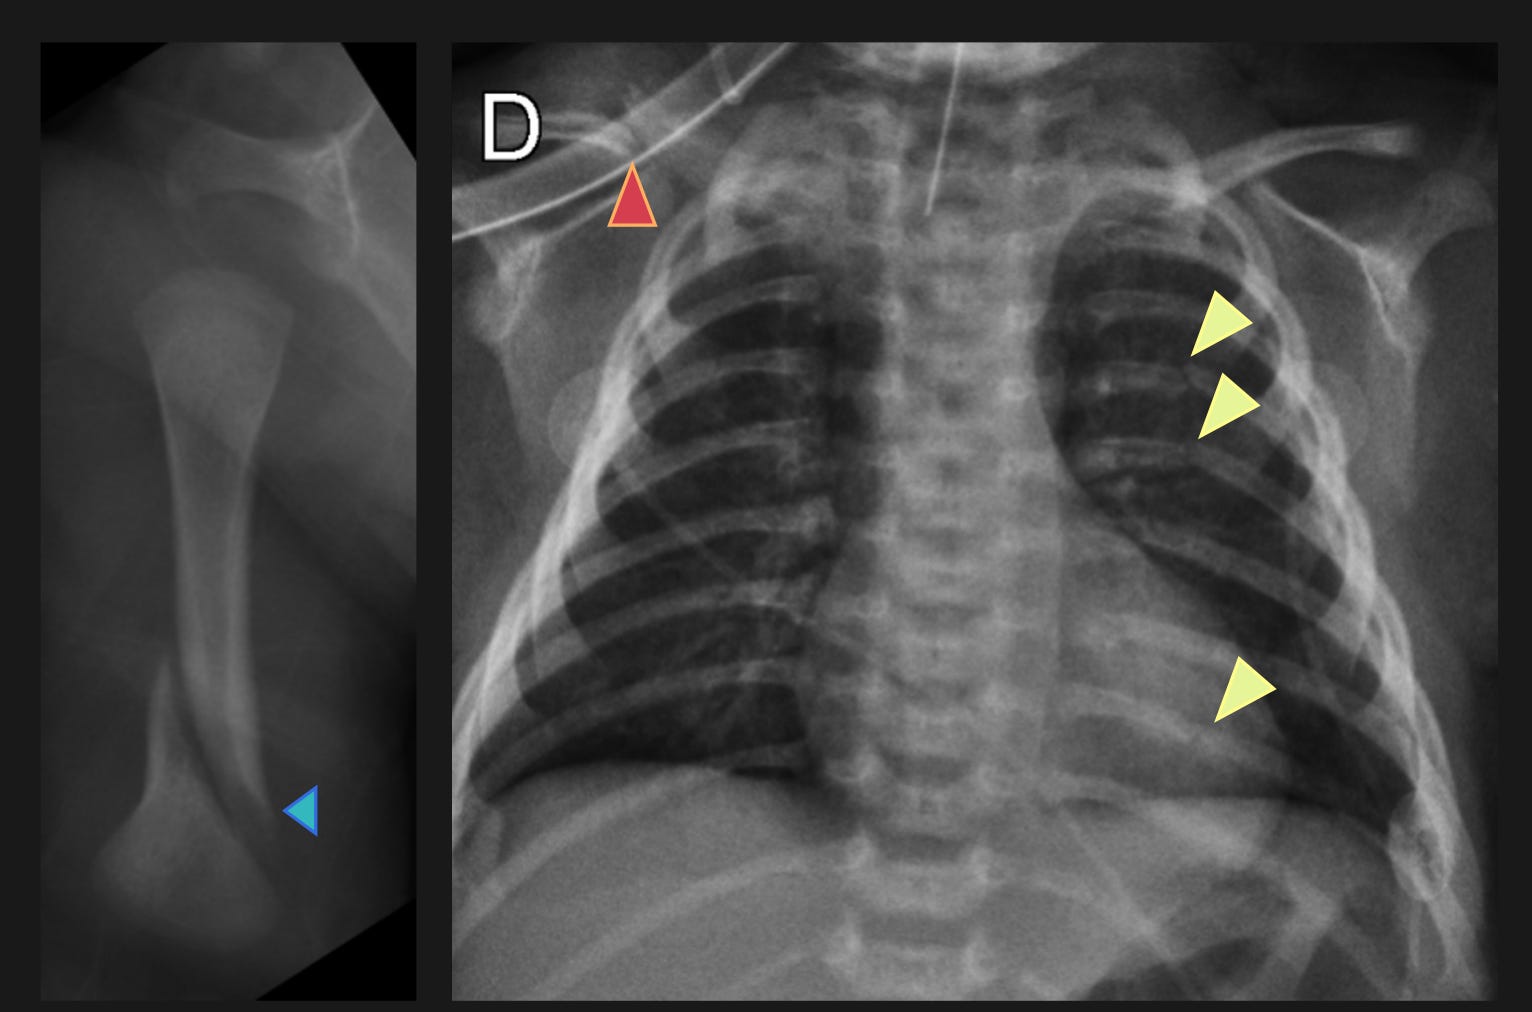

Malicious Wounding

On January 2, 2025, Erin Elizabeth Ann Strotman, a former neonatal nurse, was arrested for malicious wounding and felony child abuse after an infant suffered injuries under her care. Surveillance video in the NICU on November 10, 2024 captured Ms. Strotman assaulting a 5-month-old baby boy in the NICU and fracturing his left femur (thigh bone). Further imaging also found a fractured right tibia (lower leg bone) and multiple rib fractures.

Beyond birth trauma from shoulder dystocia or forceps delivery, many neonatal fractures fall into an “unexplained” category. However, two known risk factors for neonatal fractures include osteogenesis imperfecta (a genetic condition leading to easy bone breaks) and prematurity (a frequent reason for NICU admission). As NICU patients, babies in this case are highly likely to have been born prematurely. Among all infants, both of these risk factors are infrequent compared to non-accidental trauma, a medical way to reference child abuse. Some neonatal fractures - especially rib fractures - are “silent” and only found when getting an x-ray for another reason. Such was the case with the baby from November 10th: the team only went looking for other fractures after the baby’s thigh bone was found to be broken.